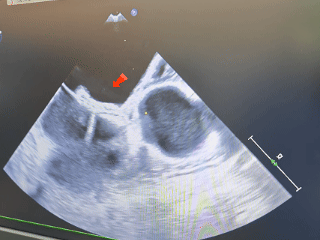

经食道超声可见

第一个缺损8.06mm

第二个缺损5.63mm

术中超声:术中经食道超声可见有两个缺损,分别为8.06mm、5.63mm,和术前超声报告对比有所偏差,两缺损距离约8.48mm。